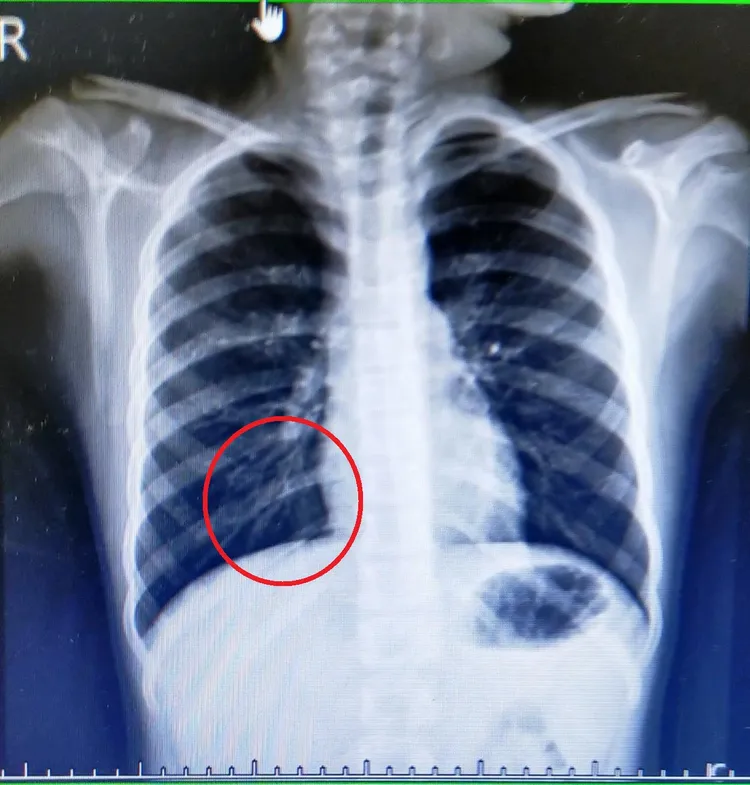

彭小妹肺部感染X光檢查。烏日林新醫院提供